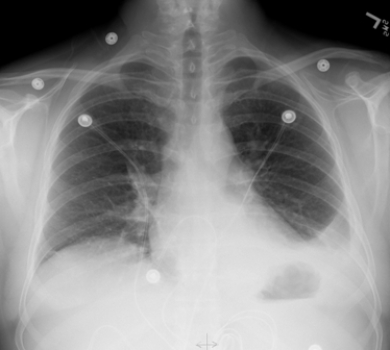

This portable AP chest radiograph shows a patient with: